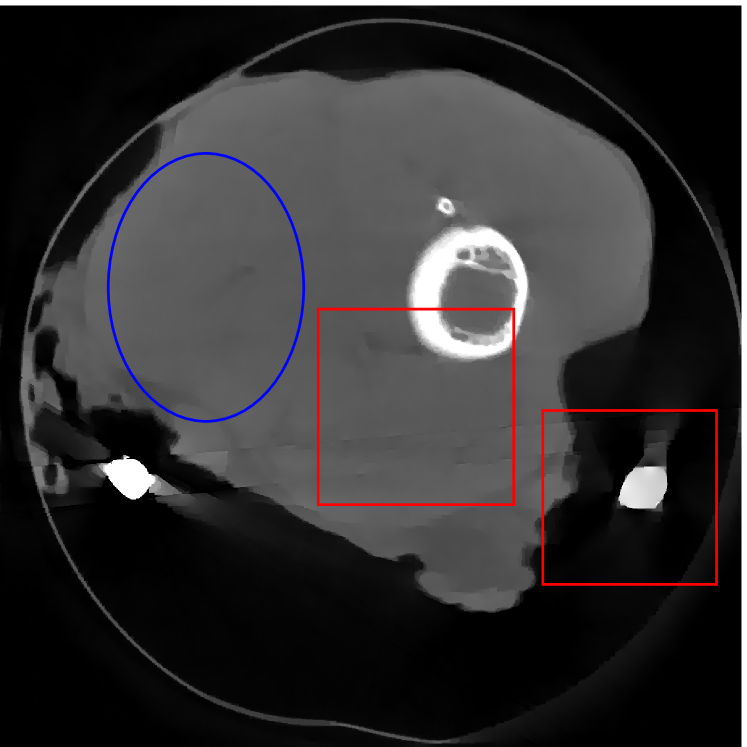

Figure 12 shows a comparison between the reconstructed image from NMAR and the unweighted JSR model. Figure 13 shows a comparison between the reconstructed images from TV-FADM and the proposed re-weighted JSR model. Zoom-in views are provided in both Figure 12 and Figure 13 for a better visual assessment. As one can see that the reconstructed images from the unweighted JSR model and TV-FADM are less noisy than NMAR as indicated by the blue ellipse curve, whereas NMAR does a better job in preserving image features and suppressing metal artifacts. However, there are also new artifacts around the metal on the right as shown in Figure 12(d). The proposed re-weighted JSR model has best overall performance in terms of feature preservation, noise and metal artifact reduction.